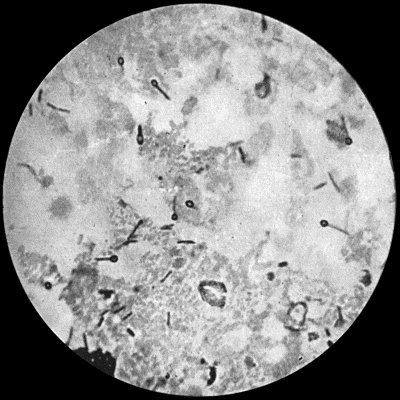

Fig. 2.—Staphylococcus aureus in Pus from case of Osteomyelitis. × 1000 diam. Gram's stain.

Staphylococcus Aureus.—This is the commonest organism found in localised inflammatory and suppurative conditions. It varies greatly in its virulence, and is found in such widely different conditions as skin pustules, boils, carbuncles, and some acute inflammations of bone. As seen by the microscope it occurs in grape-like clusters, fission of the individual cells taking place irregularly (Fig. 2). When grown in artificial media, the colonies assume an orange-yellow colour—hence the name aureus. It is of high vitality and resists more prolonged exposure to high temperatures than most non-sporing bacteria. It is capable of lying latent in the tissues for long periods, for example, in the marrow of long bones, and of again becoming active and causing a fresh outbreak of suppuration. This organism is widely distributed: it is found on the skin, in the mouth, and in other situations in the body, and as it is present in the dust of the air and on all objects upon which dust has settled, it is a continual source of infection unless means are taken to exclude it from wounds.